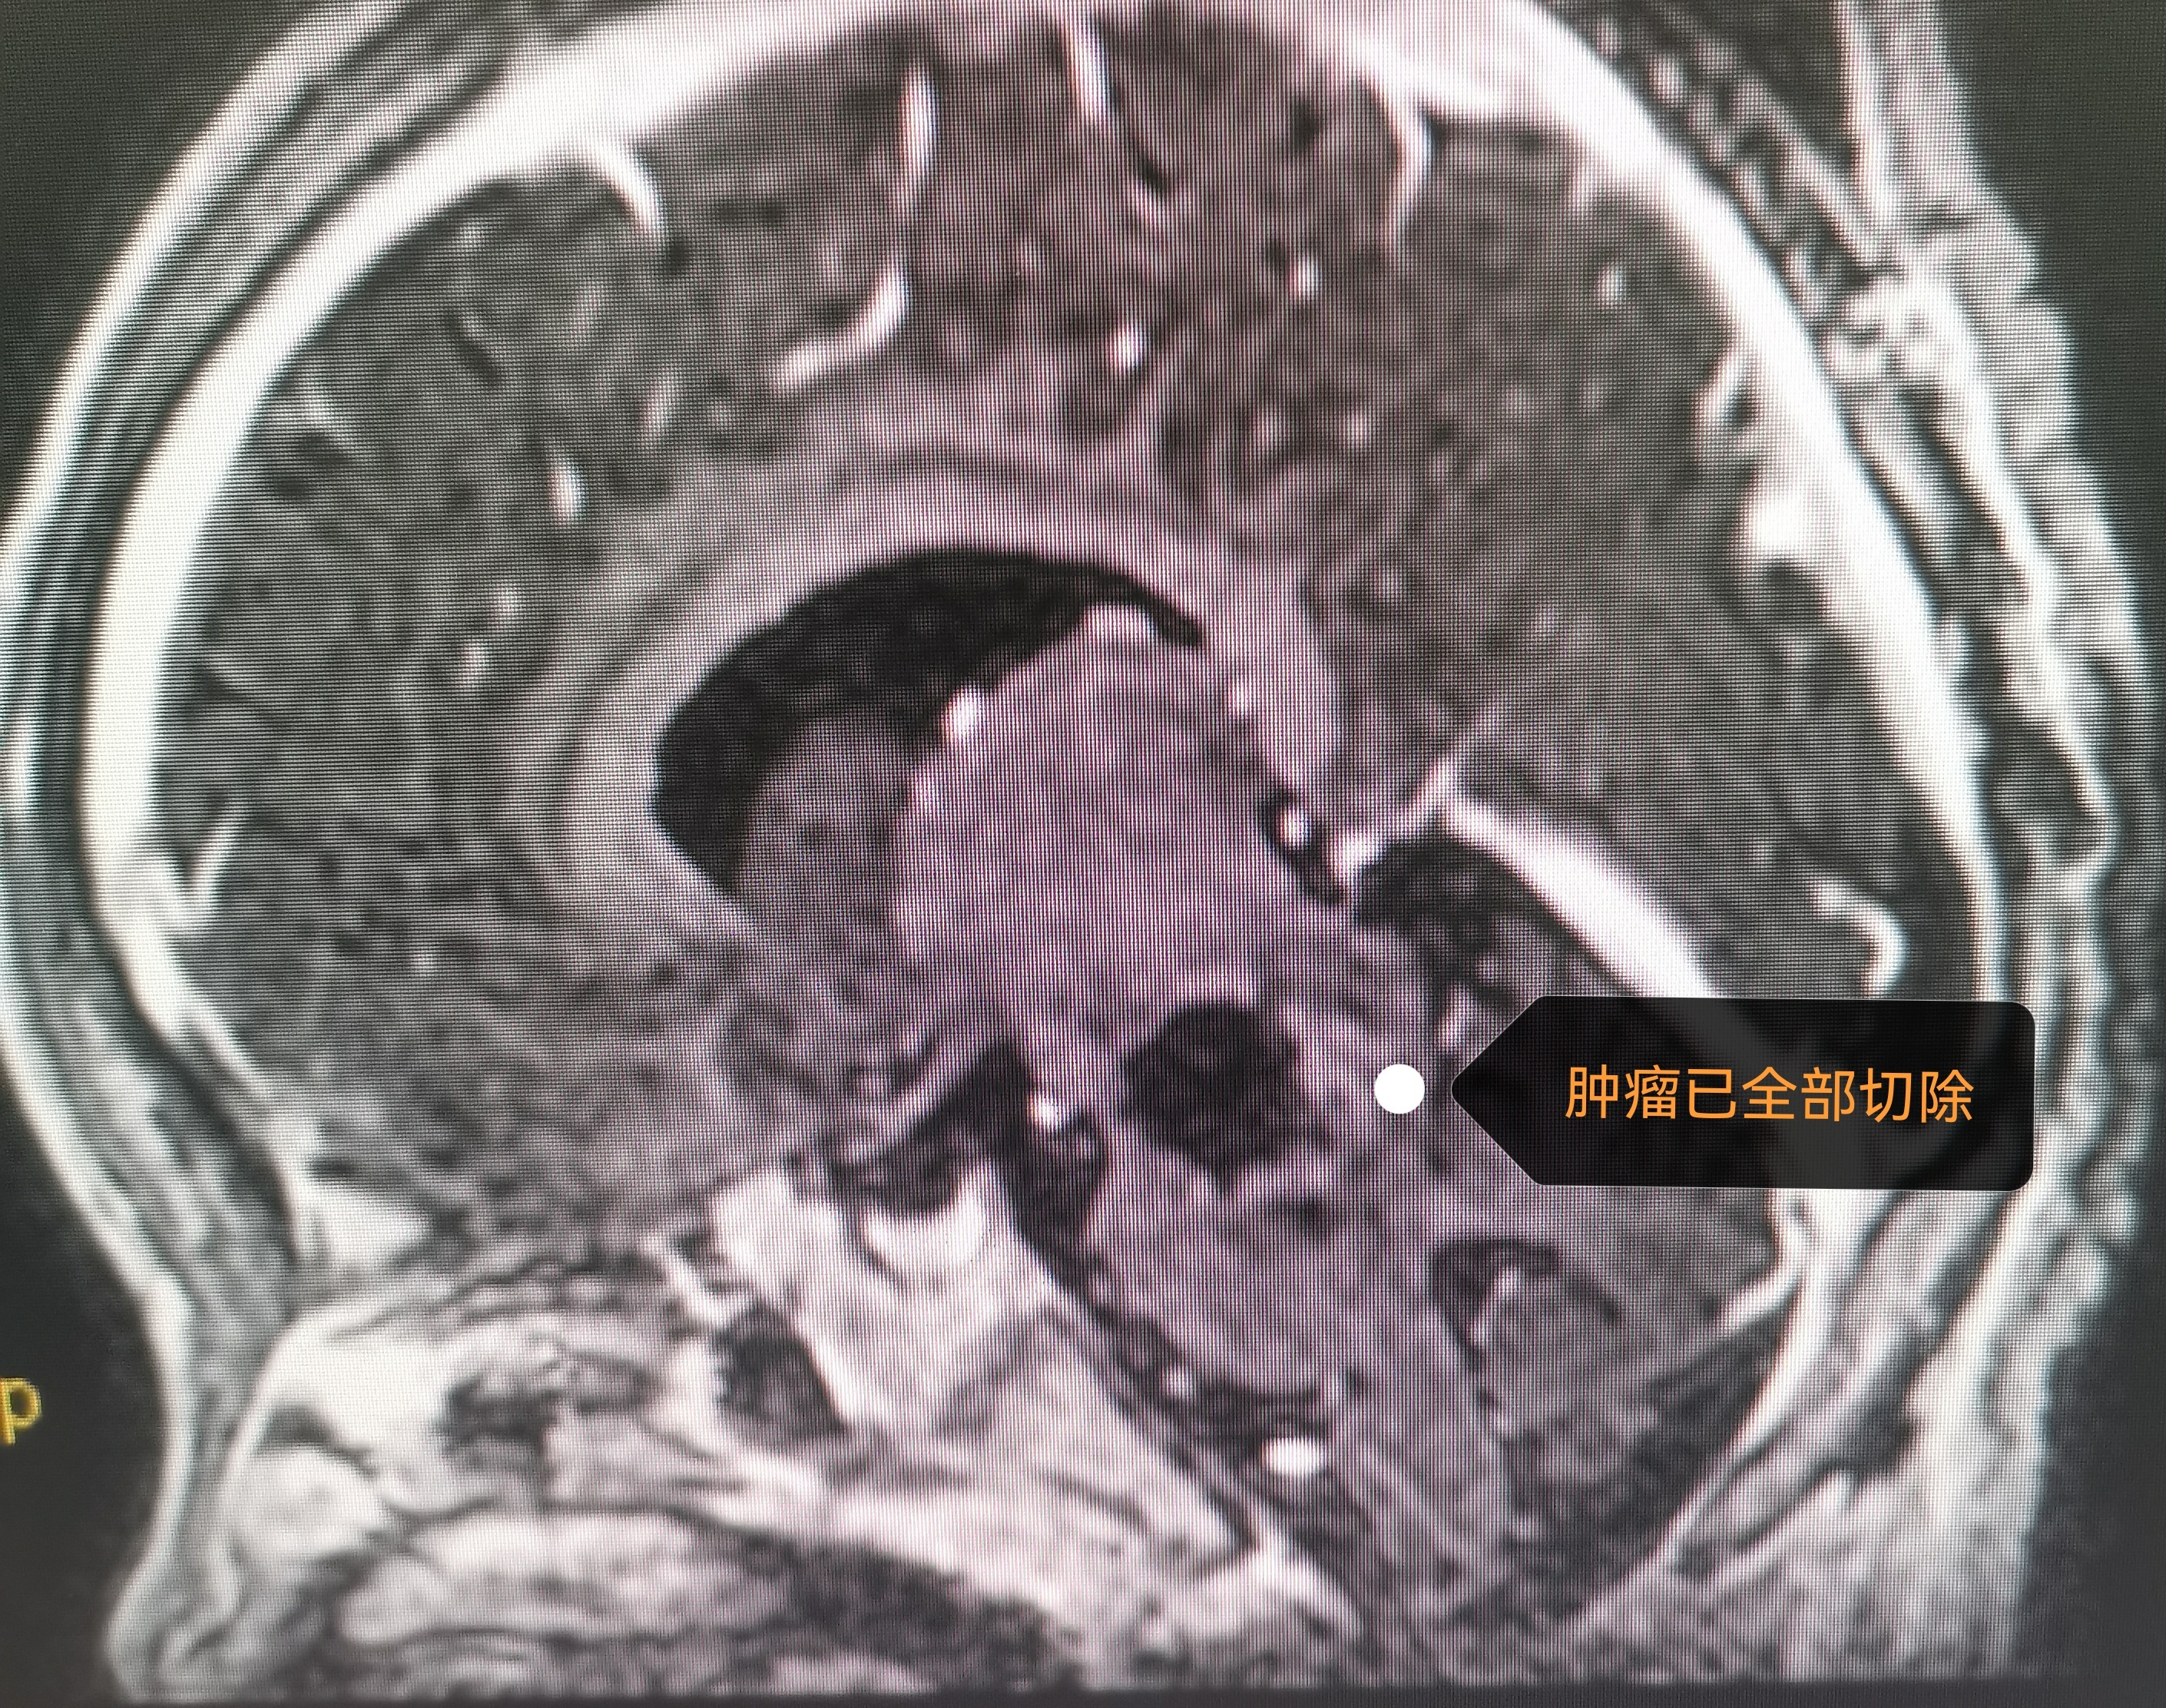

“讓子彈飛一會兒-無奈之舉”?7年前,3歲的孩子因“消瘦、發(fā)育遲緩”在外院診斷為腦干腫瘤,手術(shù)風(fēng)險極高。7年來,心大(無奈)的爸媽一直沒復(fù)查,孩子除了消瘦外癥狀不明顯。最近一周出現(xiàn)嗜睡、看東西模糊、抬不起頭。本人門診就診,復(fù)查磁共振,腫瘤較7年前長大且合并腦積水。幸運的是,這是低級別惰性(生長緩慢)生長的腫瘤,不幸的是腫瘤位于腦干。所幸手術(shù)很順利,腫瘤來源于延髓閂部,像火山一樣從腦干長出充滿四腦室。腫瘤切除滿意,閂部根基膠質(zhì)帶切除偏保守。術(shù)后肢體活動正常,無面癱、飲水嗆咳等并發(fā)癥,術(shù)后磁共振顯示腫瘤全切除,孩子順利出院,希望你能一直好運相伴[合十][合十][合十]。